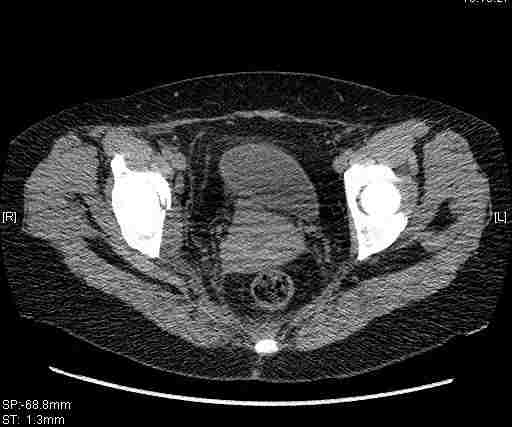

Удалось сегодня вывести пациентку в соседнюю больницу, где есть кт. Срезы сделаны только горизонтальные.

Приветствую,Антон.Рункова рядом нет,но после полученных данных КТ,обсуждали совместно.Итог обсуждения-развернутый ответ дать не получится,т.к.срезы выбраны не информативные.Если ориентироваться на данные 3D,то ,ИМХО,можно лечить на вытяжении.

Спасибо, Салават и коллеги. Насколько я понял,нужны срезы в сагитальной и фронтальной плоскостях?